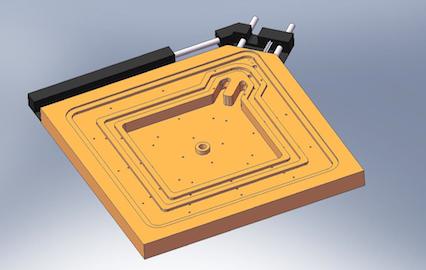

It is vital during total hip replacement surgery that the implant hardware is aligned correctly to limit the possibility of later complications. Every patient has a unique pelvic motion and Optimized Ortho developed dynamic modelling technology which provides pre-surgical information on the patient’s predicted biomechanics.

Optimized Ortho engaged Park Industrial to enable the second stage of their implant positioning system. We created surgical guides uniquely shaped to match the pelvis of each patient that were derived from X-ray and CT scan data. These guides are then fabricated from the latest 3D printing techniques using biocompatible materials.

Park Industrial developed an automated system of guide design that was created using Python scripts and the Solidworks API. This helped to realise the commercial viability of the technology.